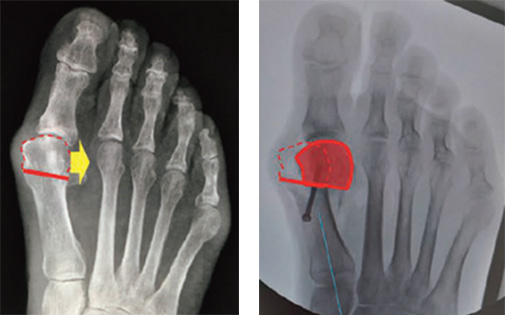

手術療法は多くの手術があり施設により異なります。一般的には第一中足骨といって、土踏まずの内側を形成する母趾の太い骨を横からみてV字に骨切りします。それを横スライドした後に金属(スクリューや面でおさえるプレート)固定を行います。

このようなやり方を、シェブロン法といいます。

なお、骨切り部は中足骨の指先側で行うのを遠位骨切りといい、根本のほうで行うのを近位骨切りと言います。イラストでは遠位骨切りをしています。